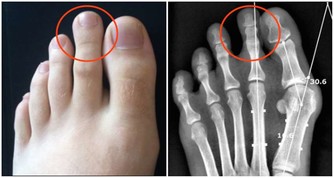

很多人飽受膝關節疼痛折磨甚至影響到日常生活。以下四種人需要重視這篇文章:關節嘎巴嘎巴響的人;腿疼的人;上下樓腿疼、膝蓋疼,有骨刺;O型腿的。